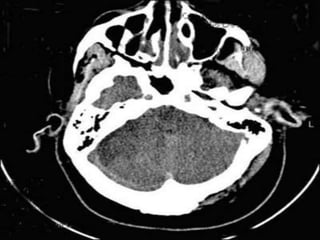

Cerebellar infarct with hemorrhagic

conversion

Vascular Insults • SubarachniodHemorrhage. • Lobar and basal ganglia bleeds. • Ischemic strokes. • Venous infarcts. • Disections

Cerebellar infarct withhemorrhagic conversion